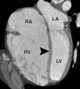

Pulmonary venous hypertension

Pulmonary hypertension (PH or PHTN) is a condition of increased blood pressure within the arteries of the lungs. Symptoms include shortness of breath, syncope, tiredness, chest pain, swelling of the legs, and a fast heartbeat. [Source: Wikipedia ]